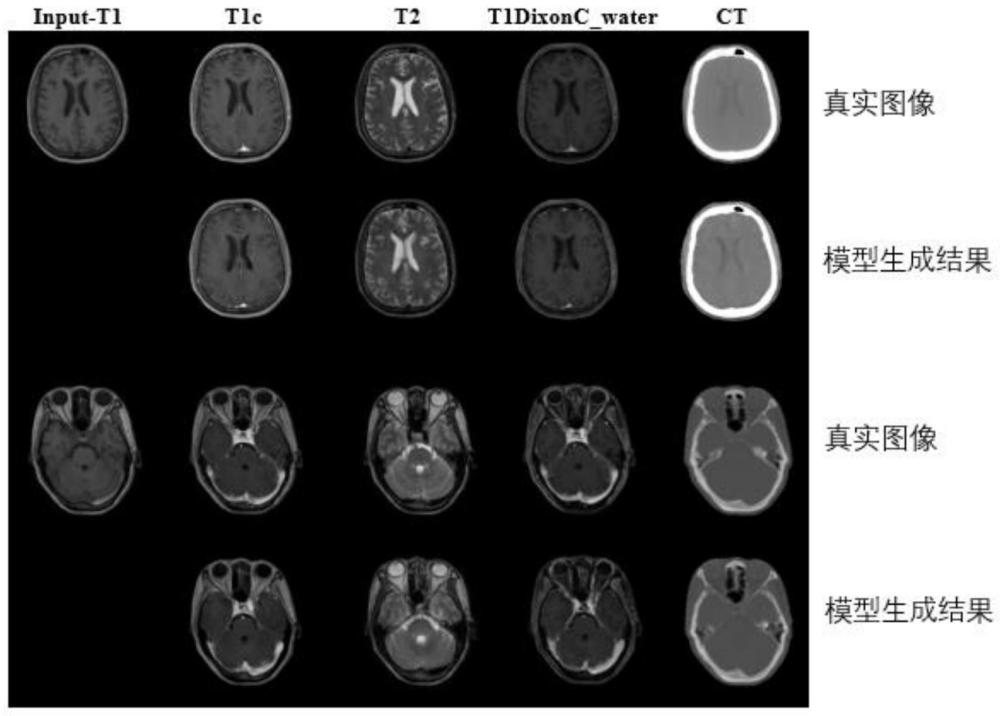

| 摘要: | 本发明涉及基于多模MRI同步生成的伪CT合成方法,属于医学图像处理领域。该方法将单个模态MRI作为输入,同时输出多个其余模态MRI和伪CT,具体步骤包括:获取单个模态MRI,输入预设的生成器,该生成器由一个共享编码器和J个解码器构成;首先获取前J‑1个解码器生成的同期多个模态的MRI,并将共享编码器和前J‑1个解码器的中间层特征融合,以获得融合特征;将第J个解码器和融合特征进一步融合,获得伪CT图像,J为自然数。本发明能够实现一对多的多模态MRI同步生成的伪CT合成,可解决临床多模态图像获取难、成本高的问题。 | ||||